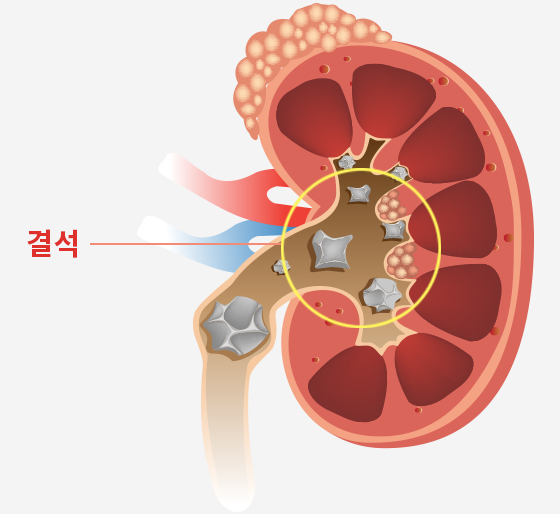

요로결석이 발생하는 원인

요 로 결 석 증 상